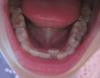

Mama06 Опубликовано 23 марта, 2013 Поделиться Опубликовано 23 марта, 2013 Здравствуйте. У моей дочери 6, 5 лет несколько месяцев назад выпал нижний фронтальный зуб. Через какое-то время прорезался постоянный, но за зубным рядом. Пошли к ортодонту. Врач посмотрела и сказала, что у дочери правильный прикус, но есть дефицит места для постоянного зуба, плотный зубной ряд и надо сделать пластинку для его расширения, чтобы постоянным зубам создать место для роста. Сняли слепок, оплатили и заказали пластинку.Через несколько дней проходили врачей для поступления в школу, в том числе и ортодонта. Ортодонт посмотрел зуб, сказал, что он еще не до конца вырос и никаких пластинок пока не надо, соседние молочные зубы выпадут и зуб сам встанет в правильное положение, а надо к нему прийти на прием в 7, 5 лет. У нескольких детей, которые ходят в группу с моей дочерью во рту подобная ситуация и никаких пластинок они не носят.Скажите,пожалуйста, нужно ли носить эту пластину, не изменится ли ситуация в худшую сторону, не раздвинется ли ровный и плотный зубной ряд до щелей? Или забрать ее через неделю и убрать подальше от греха? Спасибо. Ссылка на комментарий

Mama06 Опубликовано 23 марта, 2013 Автор Поделиться Опубликовано 23 марта, 2013 Здравствуйте. У моей дочери 6, 5 лет несколько месяцев назад выпал нижний фронтальный зуб. Через какое-то время прорезался постоянный, но за зубным рядом. Пошли к ортодонту. Врач посмотрела и сказала, что у дочери правильный прикус, но есть дефицит места для постоянного зуба, плотный зубной ряд и надо сделать пластинку для его расширения, чтобы постоянным зубам создать место для роста. Сняли слепок, оплатили и заказали пластинку.Через несколько дней проходили врачей для поступления в школу, в том числе и ортодонта. Ортодонт посмотрел зуб, сказал, что он еще не до конца вырос и никаких пластинок пока не надо, соседние молочные зубы выпадут и зуб сам встанет в правильное положение, а надо к нему прийти на прием в 7, 5 лет. У нескольких детей, которые ходят в группу с моей дочерью во рту подобная ситуация и никаких пластинок они не носят.Скажите,пожалуйста, нужно ли носить эту пластину, не изменится ли ситуация в худшую сторону, не раздвинется ли ровный и плотный зубной ряд до щелей? Или забрать ее через неделю и убрать подальше от греха? Спасибо. Ссылка на комментарий

Force Опубликовано 24 марта, 2013 Поделиться Опубликовано 24 марта, 2013 некоторое сужение челюстей имеется, но оптимальнее начинать лечение не раньше прорезывания вторых верхних резцов. И лучше все же несъемные аппараты. Так быстрее, стабильнее и правильнее. Ссылка на комментарий

Force Опубликовано 25 марта, 2013 Поделиться Опубликовано 25 марта, 2013 (изменено) Я вам озвучил тактику, которой придерживаюсь сам и многие западные доктора. Крайне редко я использую съемные пластинки и никогда в 7 лет при наличии только скученности. Возможно, у доктора другой взгляд на раннее лечение. Задайте вопрос о сроке лечения, что будет сделано пластинкой и тд. Пластинка на верхнюю челюсть или на нижнюю? Информация к размышлению Скученность на нижней челюсти при прорезывании первых нижних (!) резцов это норма Нижнюю челюсть расширить нельзя, тк симфиз (шов) закрыт уже в возрасте одного года. Можно только отклонить нижние зубы, после (!) расширения верхней, если есть показания. Но это нужно крайне редко, поскольку они сами это делают; без участия врача, но только после коррекции проблем с верхней челюстью. Расширение верхней челюсти пластинкой приводит к нежелательному наклону постоянных зубов и как следствие - различным проблемам И еще: ортодонтическое лечение - это сложный процесс с вмешательством во все структуры черепной и центральной нервной системы. Некоторые изменения крайне сложно вернуть... И необходимо четко понимать, что и зачем вы делаете. Как-то так. Изменено 25 марта, 2013 пользователем Force Ссылка на комментарий